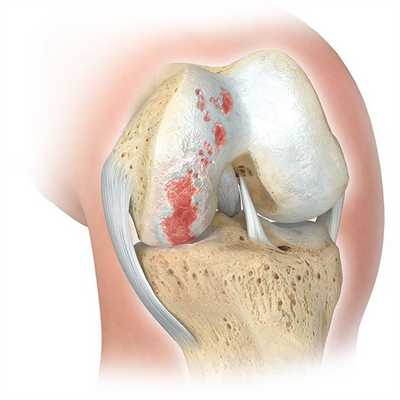

Показания к операции

Главным показанием к оперативному вмешательству является гонартроз. Это дегенеративное заболевание коленного сустава, проявляющееся постепенным разрушением хрящевой ткани и деформацией нижней конечности. На поздних стадиях гонартроза у пациентов формируются вальгусные и варусные деформации. Объем движений ограничивается, возникает хронический болевой синдром.

Вмешательство рекомендуется проводить при удовлетворительном состоянии хрящевой поверхности костей и изолированном поражении одного участка коленного сустава. Такой метод коррекции дает возможность сохранить подвижность нижней конечности у молодых пациентов.

Остеотомия коленного сустава: визуальное изображение процедуры.